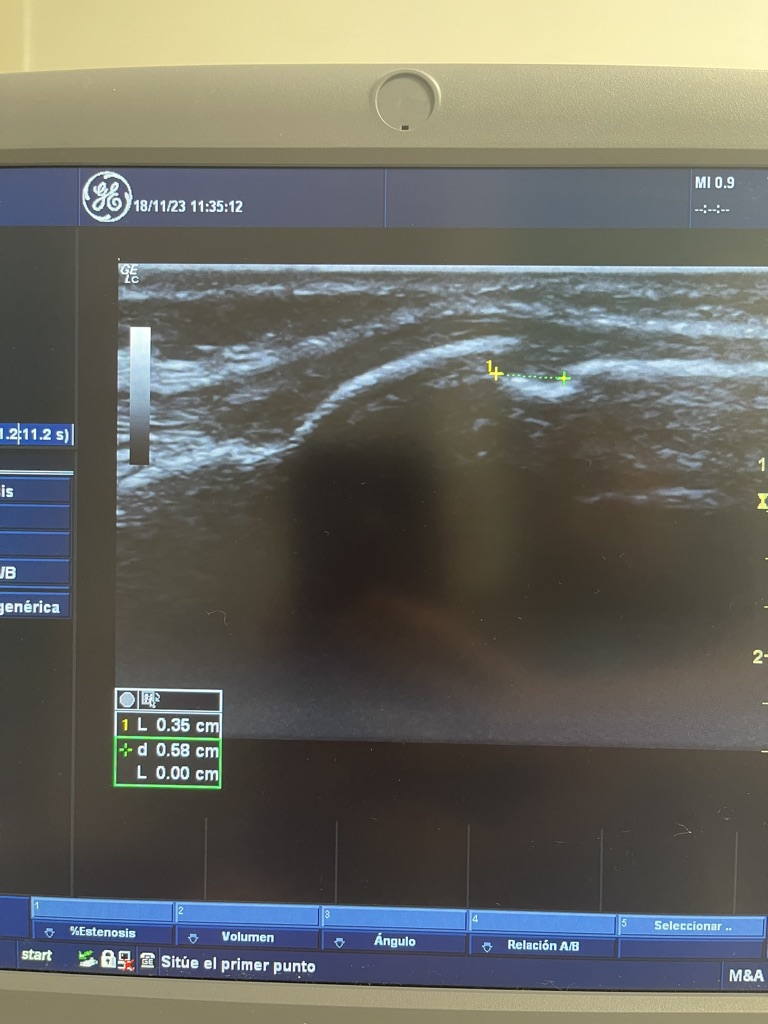

Se puede observar mediante una Radiografía lateral de Rodilla o mediante una Ecografía, donde observamos el tamaño entre otros aspectos.

En esta imagen podemos observar la aplicación de la neuromodulación.